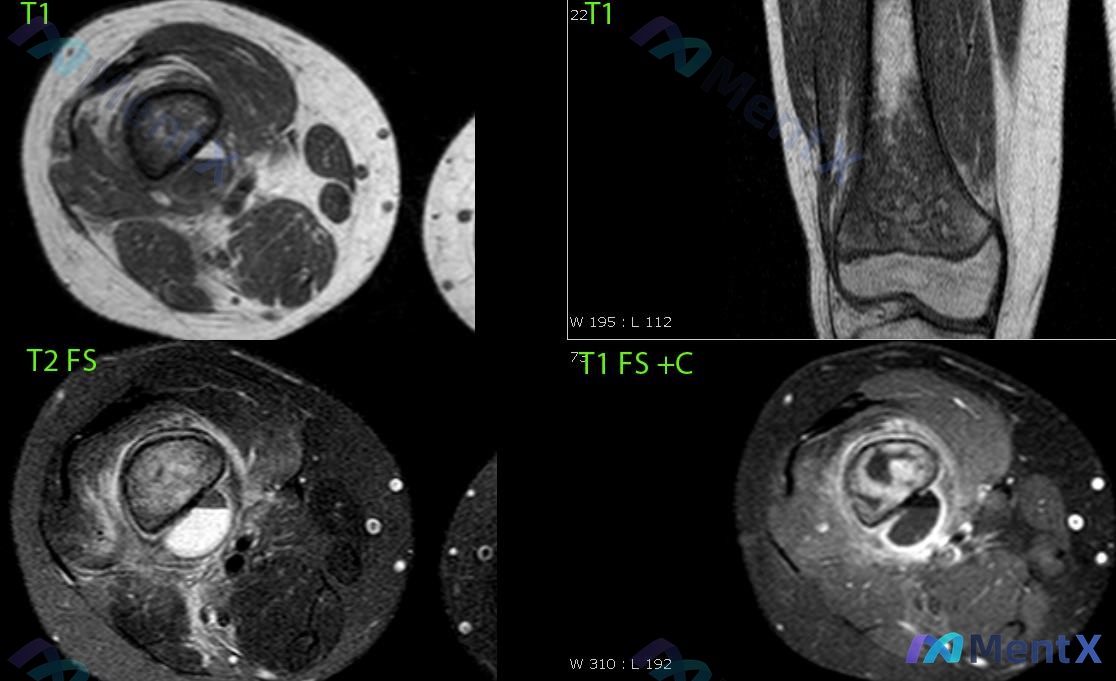

影像核心表现(MRI)

看了四个序列,整理关键阳性和阴性:

- 病灶位置:大腿中下段后方、股骨与肌肉间隙内,未在膝关节腔内

- 形态:类圆形,边界清晰,有完整包膜,对周围肌肉仅推挤、无侵犯

- 信号特点:

- T1:等/稍低信号

- T2脂肪抑制:极高信号(典型液性)

- T1脂肪抑制增强:仅囊壁及分隔环形/线状强化,中心液性区无强化,无明显实性成分

- 重要阴性:

- 股骨远端、胫骨近端骨质连续,无明确骨皮质破坏或关节面下异常

- 膝关节腔无明显积液

- 周围无弥漫性软组织水肿